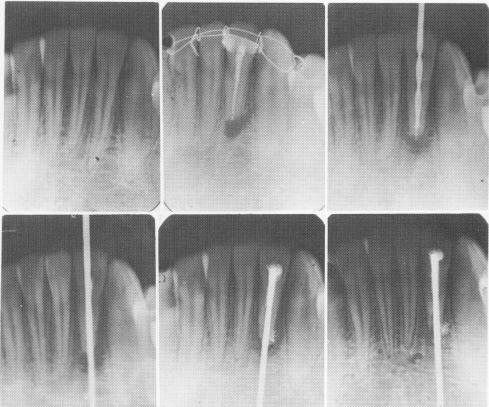

Fig. 13-11. A number of months after an apicoectomy and gutta-percha root canal filling was done on a right loose lateral incisor, the filling was removed and replaced with an endodontic root stabilizer. Within 1 year after its insertion the radiolucency completely disappeared. (Courtesy Dr. V. Bloch.)

The two-stage endodontic pin implant process is clearly illustrated radiographically by two cases. In Fig. 13-11 a right lateral incisor had a periapical lesion and was loose as a result of an accident. The nerve was removed, an apicoectomy was per-formed, and the tooth immobilized with .010 ligature wire. Within a year after endodontic stabilizer insertion, the periapical radiolucency had disappeared.

Another patient fractured a right mandibular central incisor in an automobile accident, severing the nerve in the canal. Pain and looseness of the coronal half of the tooth was obvious. Removal of the damaged nerve and insertion of an endodontic root stabilizer rigidly held the coronal portion of the tooth to the root (Fig. 13-12).